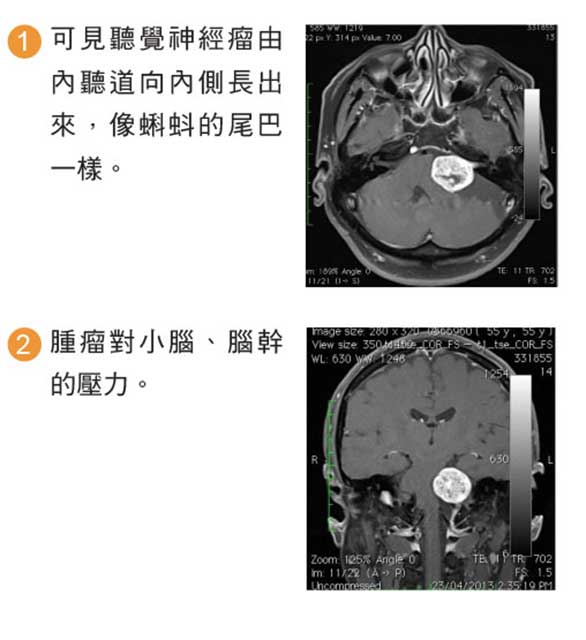

磁力共振影像診斷

磁力共振醫學影像檢查,有助於明確診斷及鑑別小腦腦橋角區域的腫瘤,例如腦膜瘤、表皮樣囊腫、三叉神經鞘瘤等的鑑別。

聽覺神經瘤的磁力共振影像特點:

聽覺神經瘤的磁力共振影像特點: